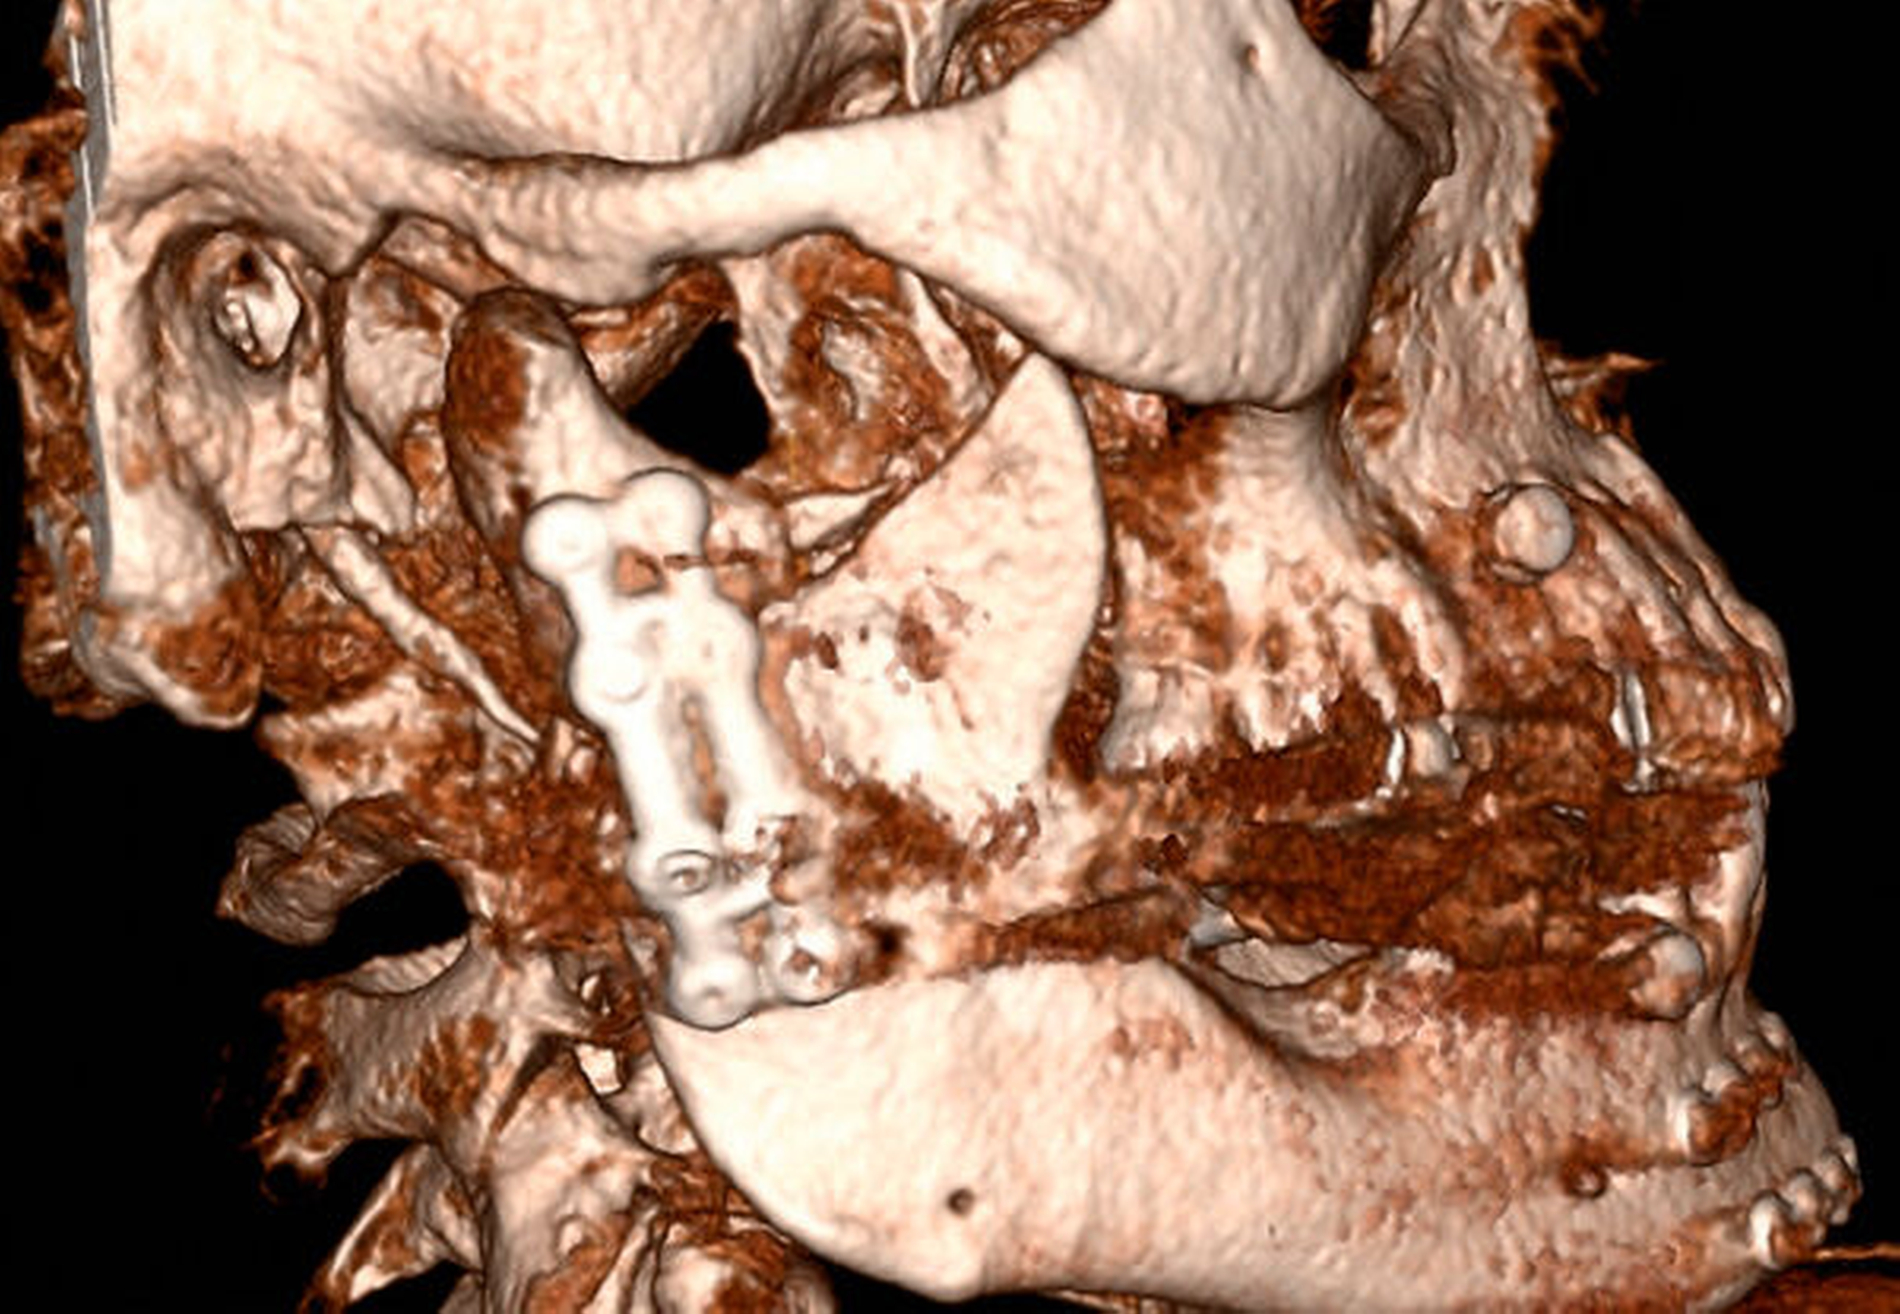

Auch unter Beachtung des langen Zeitraums zwischen dem Frakturhergang und der Vorstellung wurden mit der Patientin die Optionen des Belassens der Situation, einer kieferorthopädischen, einer prothetischen und einer chirurgischen Therapie mit den jeweiligen Vor- und Nachteilen ausführlich besprochen. Sie entschied sich für die chirurgische Option, da sie sich hierdurch am schnellsten Besserung erhoffte. Daher erfolgte im Rahmen einer Intubationsnarkose die Darstellung der beiden in Fehlstellung verheilten Frakturen über einen präaurikulären Zugang (Abbildung 4). Mittels Piezochirurgie folgte die Re-Osteotomie im Bereich der ehemaligen Brüche. Eine intermaxilläre Fixierung durch Drahtligaturen und IMF-Schrauben ermöglichte anschließend eine funktionsstabile Osteosynthese mittels Miniplatten in Okklusion (Abbildungen 5 und 6).

Aufgrund der Fehlstellung mit verkürzter Abstützung war bereits präoperativ die Notwendigkeit der Bruchspaltaugmentation abzusehen, die im Anschluss mit Beckenkammspongiosa durchgeführt wurde (Abbildung 7). Postoperativ zeigte sich ein suffizientes Ergebnis der osteosynthetisch gesicherten Reposition mit guter Okklusion.